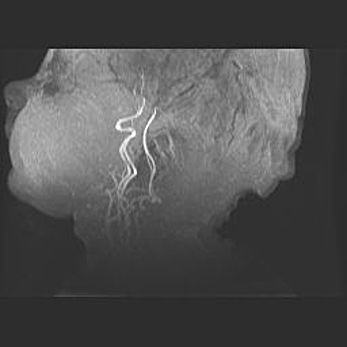

Подострая гематома правой гемисферы мозжечка.

Наружная гидроцефалия.

Возраст: 15 дней

Вес: 3100 г

Пол: женский

Окружность головы: 37 см

Срок гестации: 35-36 недель

При открытой наружной форме гидроцефалии у новорожденных расширяются и переполняются субарахноидные пространства.

Кровоизлияния в мозжечок имеют две клинико-анатомические формы: полушарные гематомы и кровоизлияния в червь.

К появлению этой патологии может привести: повреждения головного мозга, возникающие в результате асфиксии и гипоксии плода при беременности, или травмы во время родов. Редко гематома мозжечка может быть результатом первичной коагулопатии и сосудистой мальформации, диссеминированном внутрисосудистом свертывании, изоиммунной тромбоцитопении.